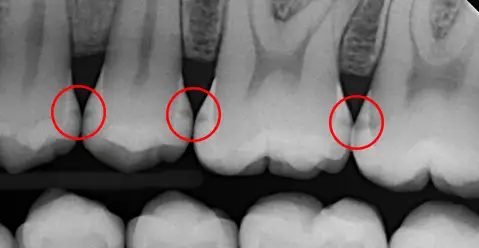

2. No digital radiographs (x-rays)

Having access to radiographs (x-rays) is very important in diagnosing early decay. Back in the day, you couldn’t take a digital radiograph and work out exactly what was happening inside the tooth then and there in the dental surgery. Instead, the x-ray film had to be sent away to be developed – similar to old photos. This meant that on the day, dentists had to rely more on what they could see in the mouth and the patient’s symptoms.

Catching decay early, often with the help of radiographs (x-rays), because early decay isn’t always visible to the eye.